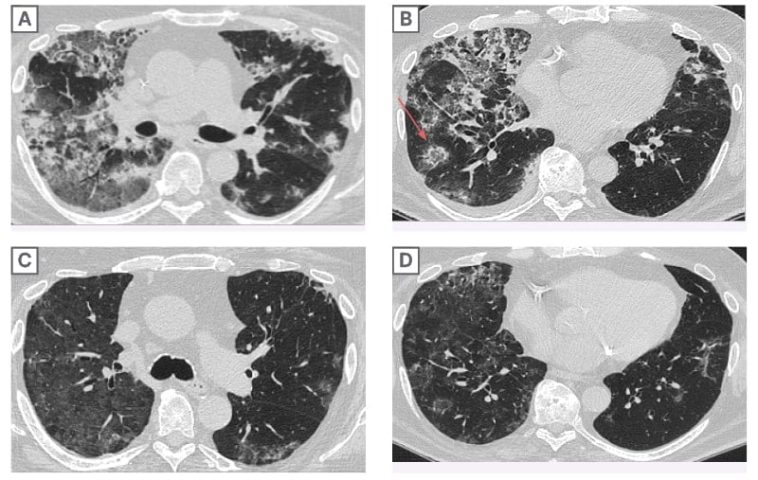

A series of diagnostic tests were carried out, including chest X-rays and a high-resolution CT scan. These imaging studies revealed bilateral scattered opacities and ground-glass appearances—findings that can easily be mistaken for pneumonia or pulmonary edema. Overlapping symptoms and imaging results make it a nerve-racking task for clinicians, highlighting the need to probe deeper into a patient’s medication history.

Imaging studies are indispensable when it comes to identifying pulmonary infiltrates. In our case, chest X-rays and CT scans played a part in outlining the spread and character of the lung involvement. Ground-glass opacities, described as a hazy area with fine shades of density on the CT scan, are particularly important in showing the patient’s underlying lung condition.

It is critical, however, to note that these radiological findings can be seen in many lung conditions. Therefore, clinicians need to figure a path through subtle details provided by imaging, combined with other clinical information like recent medication changes and laboratory findings, to reach a definitive diagnosis.

- Imaging Characteristics: Bilateral ground-glass opacities and centrilobular nodules are clues, yet they can also be present in diffuse alveolar damage. A comprehensive analysis of imaging studies is therefore super important.